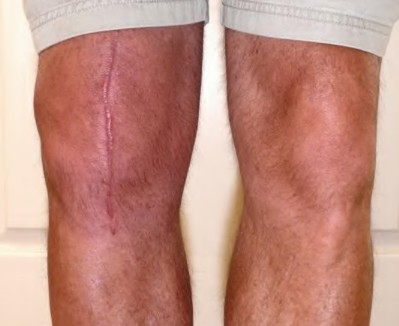

A 67-year-old diabetic male presents 4 months status post right total knee arthroplasty (TKA) complaining of pain and stiffness for the last four weeks. A clinical photograph is shown in Figure A. Radiographs and a bone scan are shown in Figures B, C and D. Blood work shows an ESR of 14mm/hr (normal 0-12mm/hr) and a CRP of 2mg/L (normal 1-3mg/L). Knee aspiration yields WBC of 1000, 30% PMNs, and a negative gram stain. He finished a 14-day course of antibiotics prescribed to him by his primary care physician one week ago. Which of the following is the most appropriate next step in management?

Figure A is a clinical photograph demonstrating a swollen, erythematous right knee with a well-healed incision from a previous TKA. Figure B and C are AP and lateral radiographs of the right knee with no obvious acute findings. Figure D is a bone scan demonstrating increased uptake in the post-operative knee, which is consistent with the 4 month follow-up.